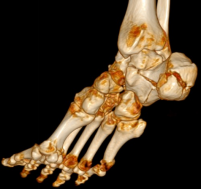

回到前文所述的患者程某,其X线片及CT检查提示其骨折系波及关节面的严重粉碎性骨折,具有明确的手术指征。

但其伤足局部皮肤软组织条件较差,如冒然采用常规开放手术治疗,术后出现上述伤口相关并发症的风险较高。为了能在达到骨折解剖复位的同时,最大程度地避免上述开放手术的风险及潜在并发症的出现,骨科中心全体医师充分讨论、手术专家团队细致规划,最终决定施行机器人辅助下的微创内固定手术。